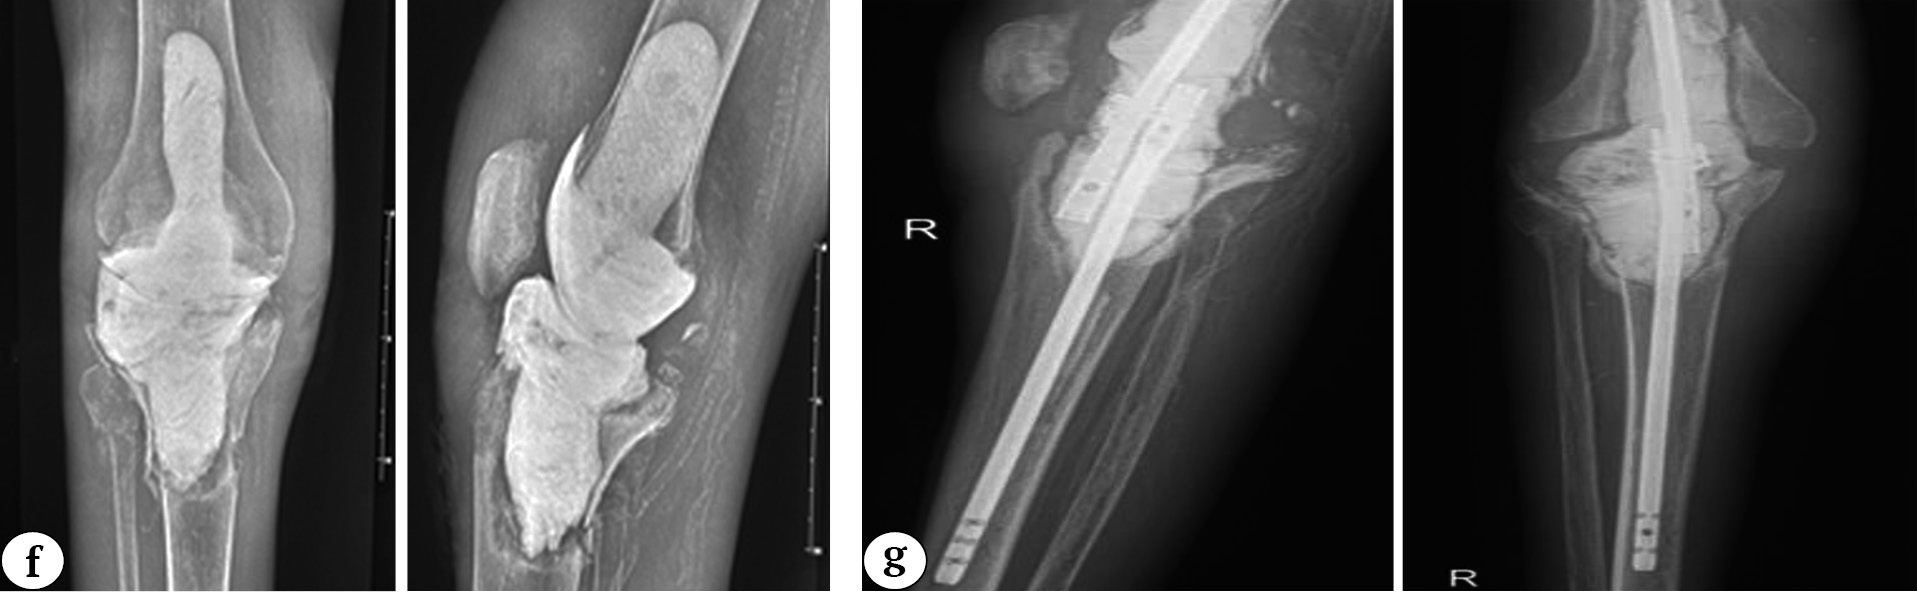

Fig. 3 (f, g). A 32-year-old man with secondary osteoarthritis of the right knee. Concomitant diseases: end-stage chronic kidney disease (5D stage), chronic hemodialysis for 7 years, type 1 diabetes: f — X-rays 3 years and 7 months after knee replacement (an articulating spacer was implanted); g — X-rays 4 years and 2 months after primary knee arthroplasty (an articulating spacer was replaced with a block spacer due to recurrent infection)